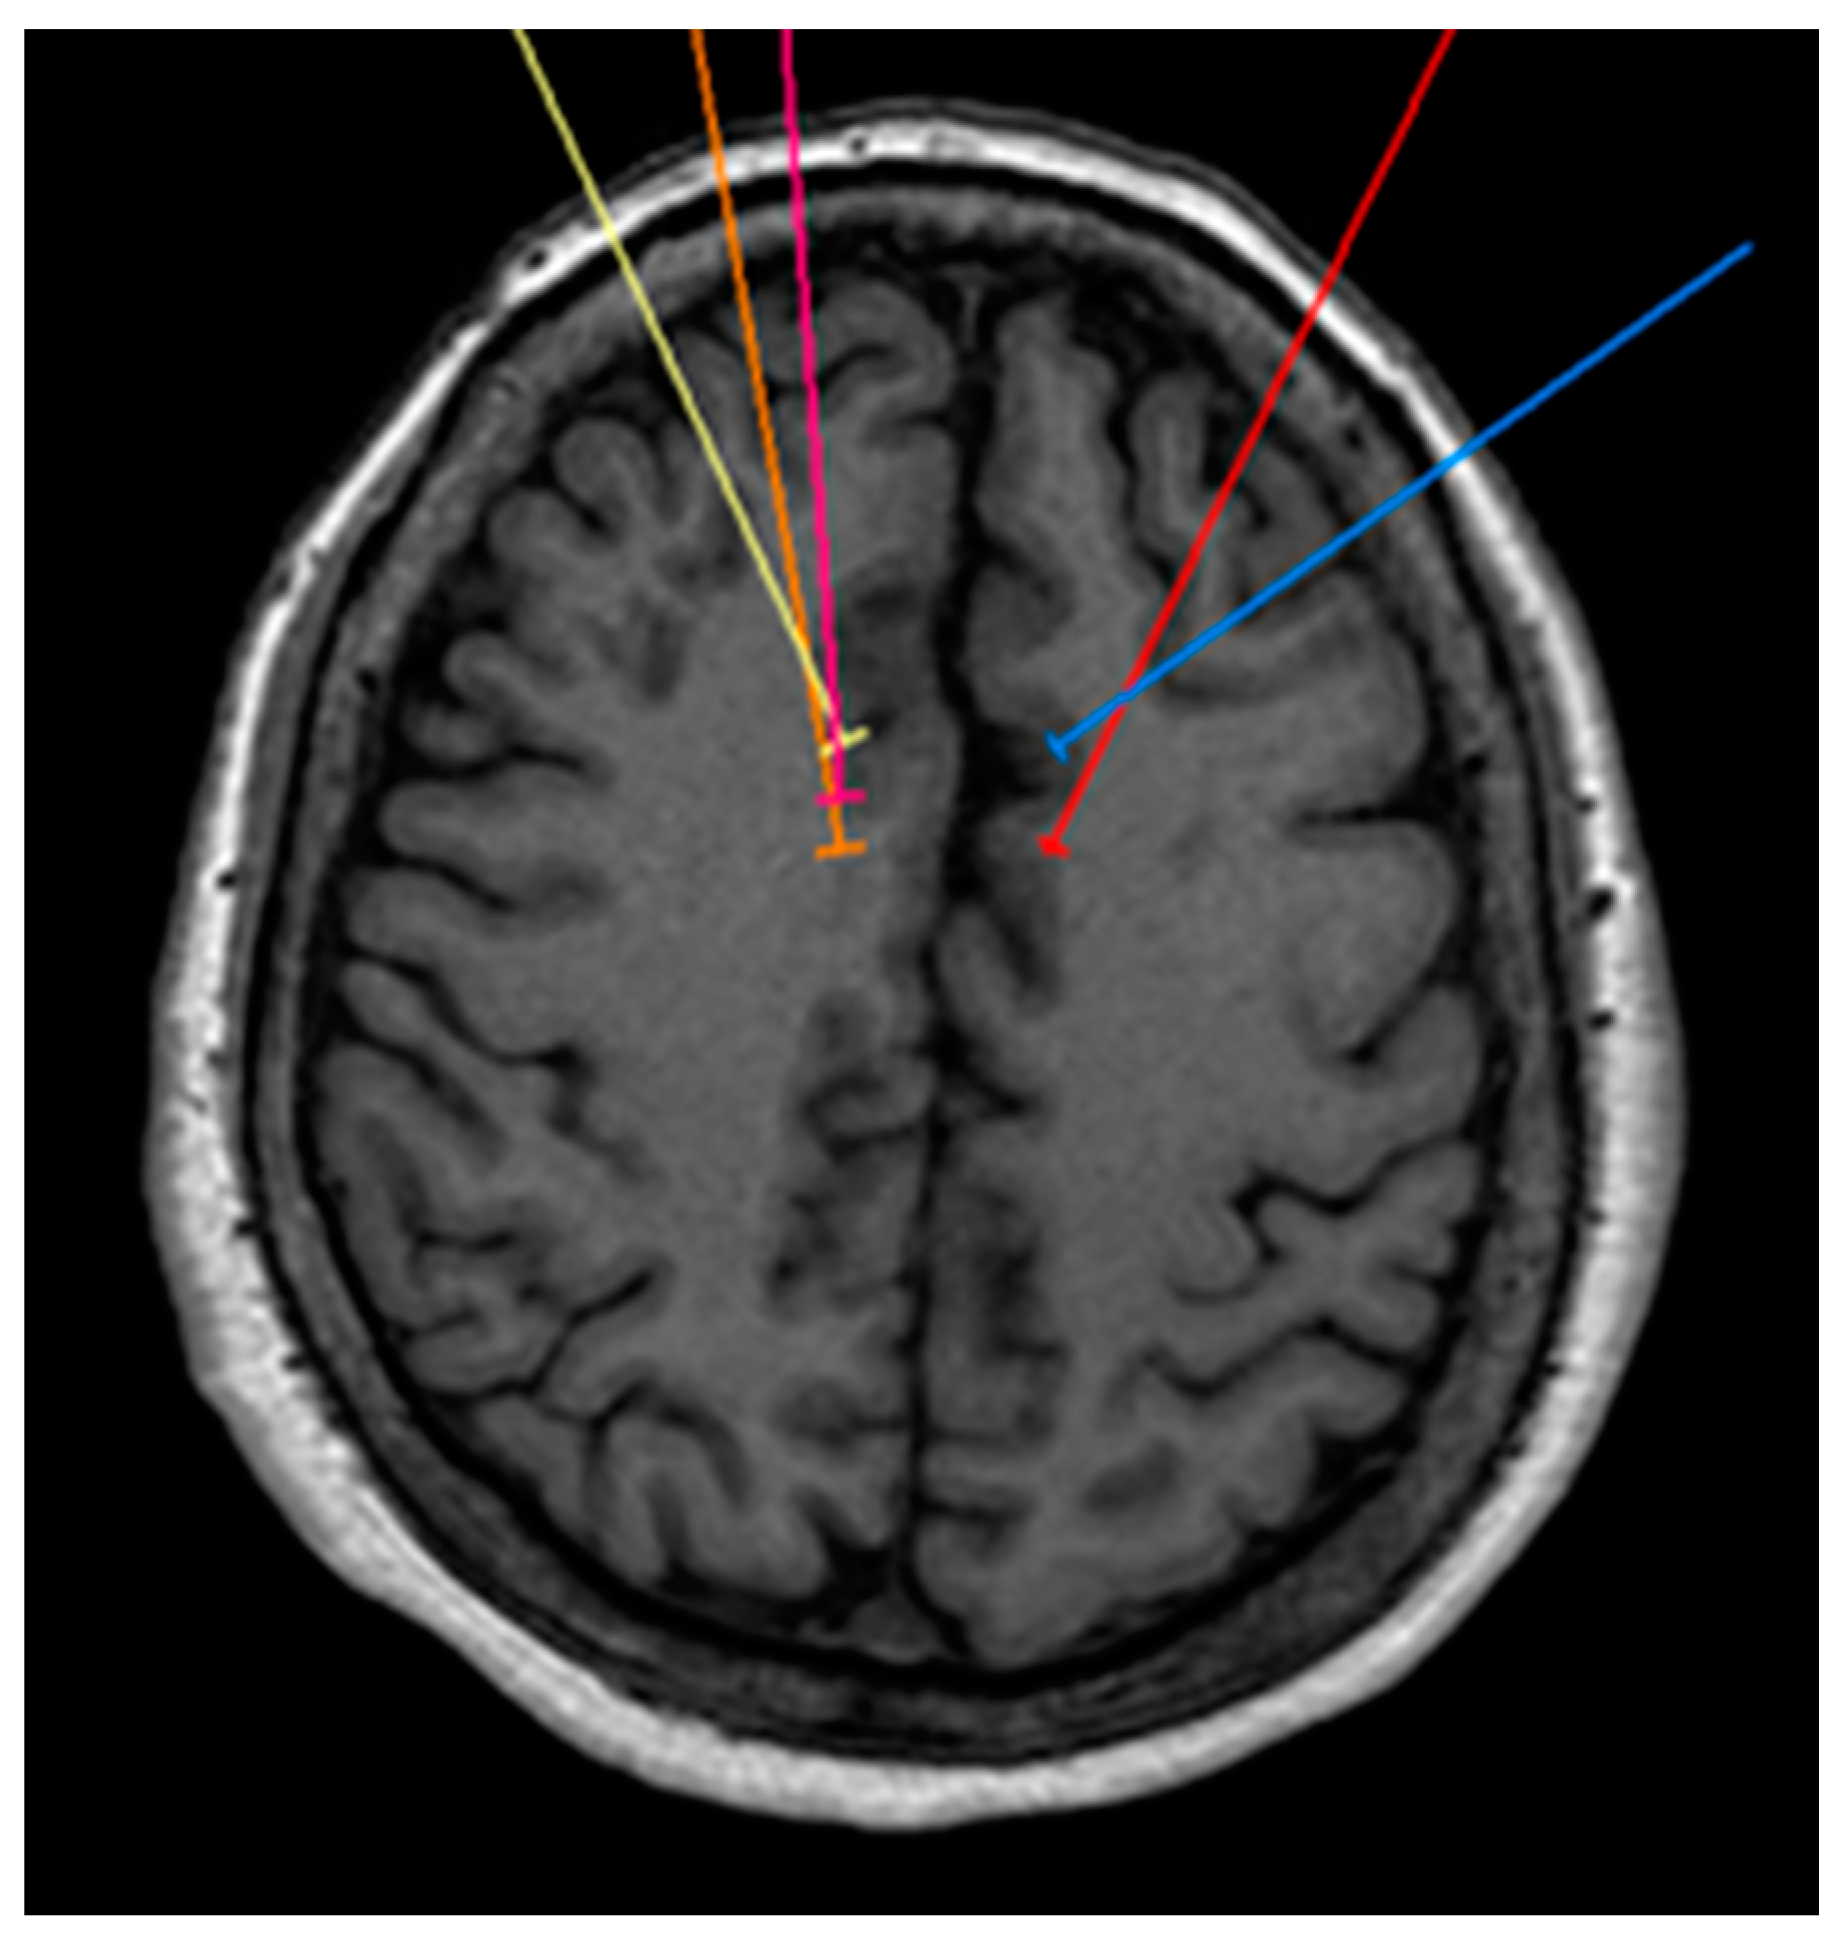

Figure 4.

Bilateral projection of cross-sectional cingulotomy from patient 3.